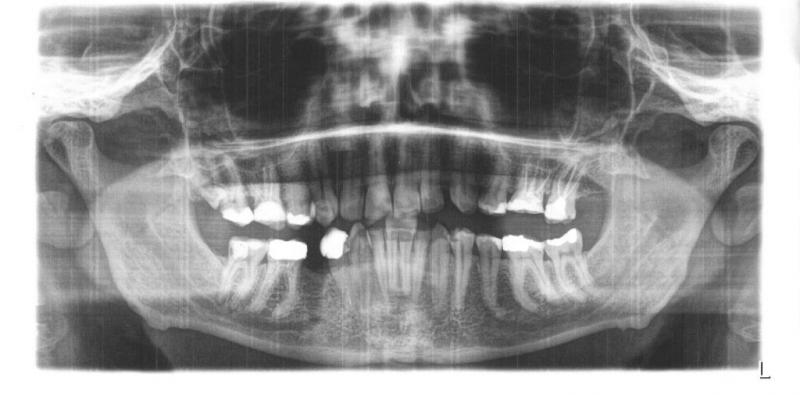

Und endlich ein Panorama. Leider nur ausgedruckt. Hat man ein Recht auf die digitalen Bilder?

Könnten Sie es mir bitte befunden? Bin 43J., männlich, guter Esser.

Was gehört hier gemacht? Wo wurden sie das preislich einordnen? Sind die Nebenhöhlen in Ordnung? Wie sehen die alten WB aus?

[ATTACH=CONFIG]1881[/ATTACH]

Bessere Auflösung: